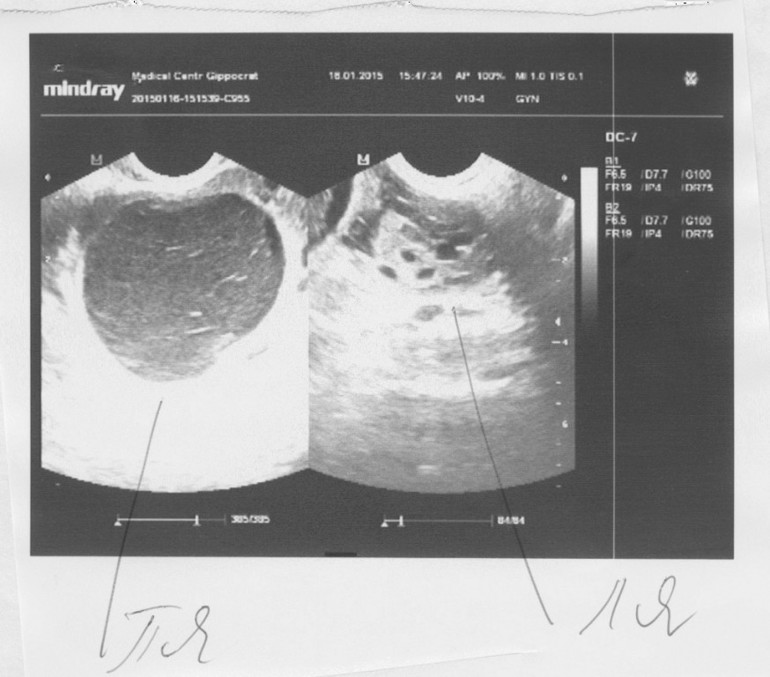

Девоньки, собственно вот и вопрос)))))) О не отслеживала. Посл. М 14.12.14 г. на 17 дц цикла была на узи, узистка ДФ не увидела. Киста моя - как яблочко наливное 55х54 мм.

Фото с узи под кат

У вас и правда как яблоко)))